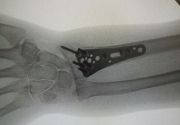

4. Displaced fracture of distal end of the right radius (wrist fracture) in a 63-year-old female.

Treatment. Open reduction internal fixation

I. Before operation, anteroposterior x-ray of the wrist II. Before operation, lateral x-ray of the wrist IIA. Day of procedure, lateral view IIB. Day of procedure, anteroposterior view